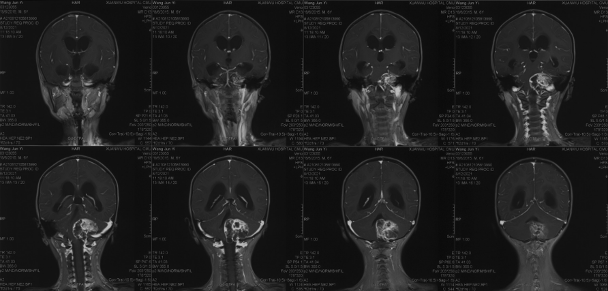

1-year postoperative imaging and follow-up

Postoperative enhanced MRI

Postoperative follow-up 1 year enhanced MR